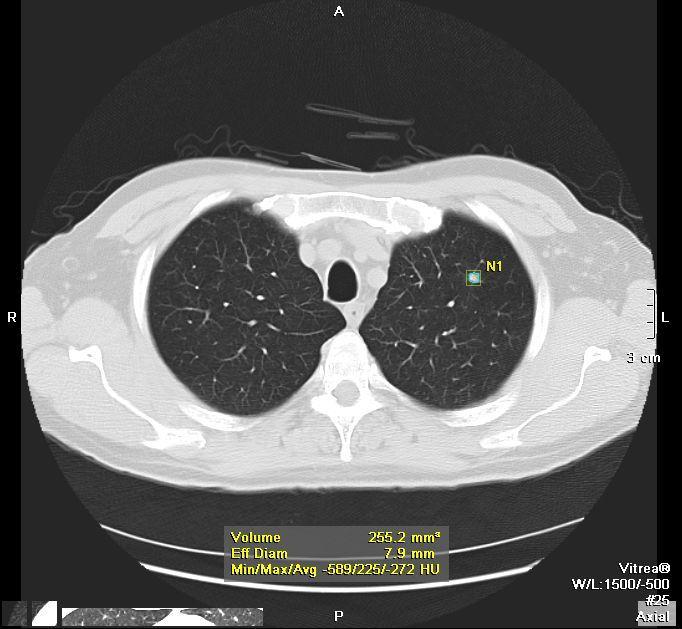

Αξονική τομογραφία χαμηλής δόσης όπου φαίνεται αρχόμενος καρκίνος μεγέθους 1 εκατοστού. Ο ασθενής θα χειρουργηθεί έγκαιρα και θα ιαθεί.